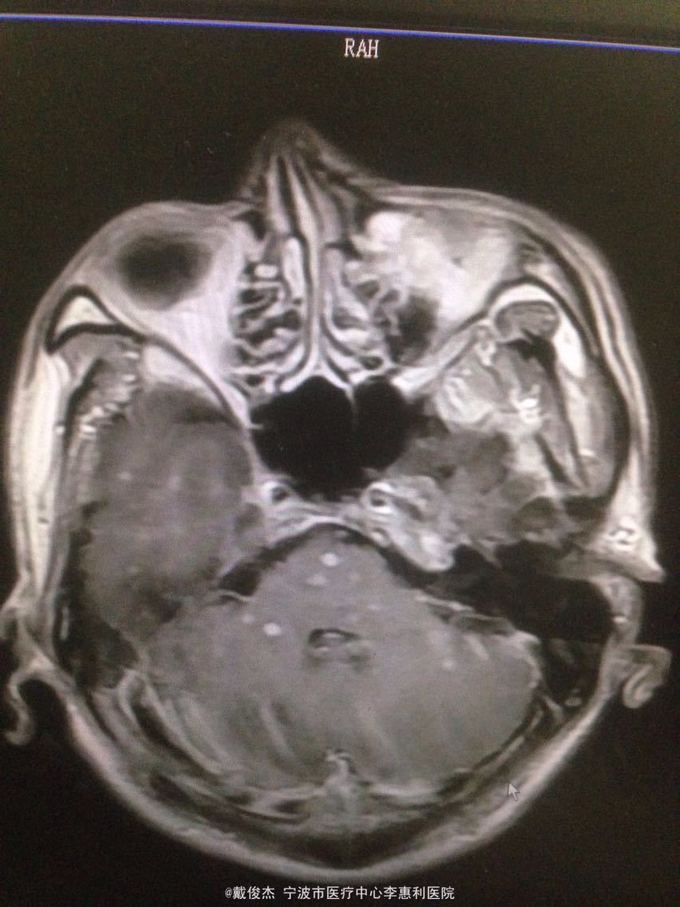

查体:神志清,双肺啰音,颅神经阴性,颈抵抗,四肢肌力正常,双巴氏征阴性 辅查:脑脊液压力380mmH2O,细胞4100/ul,多核90%,单核10%,蛋白223mg/ml。胸部CT示:两肺多发粟粒小结节。头颅MRI示:双侧大脑半球、脑干、小脑多发病灶。

诊断:结核性脑炎,肺结核 处理:抗痨治疗,激素,降颅压,保护神经和对症支持治疗